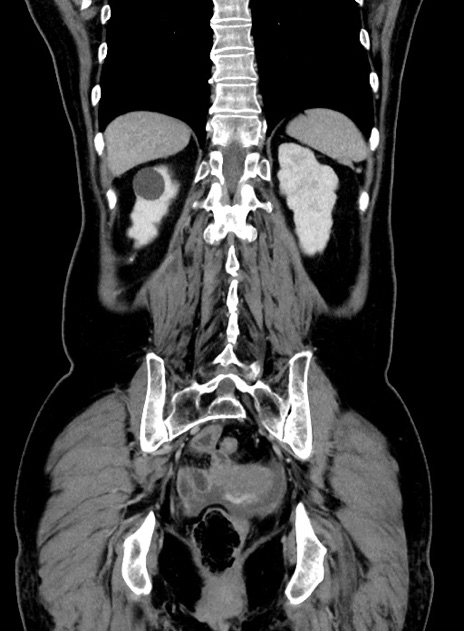

症例9(冠状断像)

【症例】 60歳代女性

【主訴】むかつき、みぞおちの痛み

【現病歴】3日前よりむかつきがあり、食事がとれない。

【既往歴】糖尿病

【身体所見】発熱なし、心窩部圧痛軽度あるも、腹膜刺激症状なし。

【データ】WBC 7400、CRP 1.92